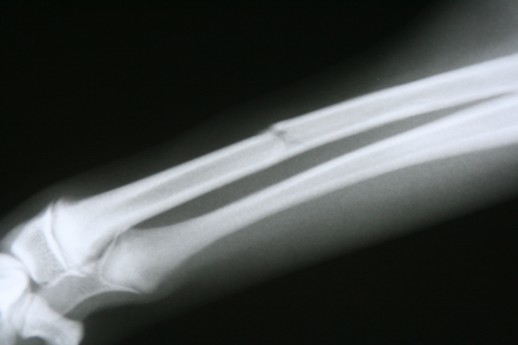

What type of fracture is this?

Greenstick Fracture